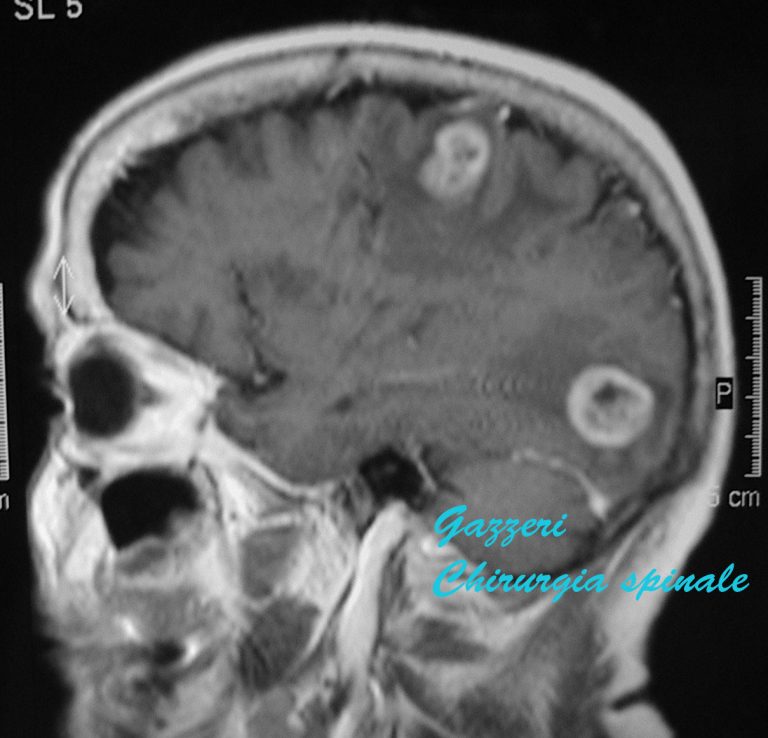

Metastasi cerebrali Chirurgia Spinale

Metastasi: sintomi e diagnosi. La diagnosi di metastasi può essere complicata, poiché i sintomi possono variare in base alla localizzazione e alle dimensioni delle metastasi.. quando il cancro si è diffuso al cervello; mancanza di respiro e tosse, quando il cancro si è diffuso ai polmoni; ittero (caratterizzato da colorito giallo della.. Le metastasi cerebrali si verificano quando le cellule provenienti da un tumore primario insorto in un’altra parte del corpo migrano , localizzandosi nel cervello. La metastasi può svilupparsi in una sola parte del cervello o interessare più parti contemporaneamente. I tumori che più frequentemente generano metastasi cerebrali sono il tumore del polmone, il tumore della mammella, il.